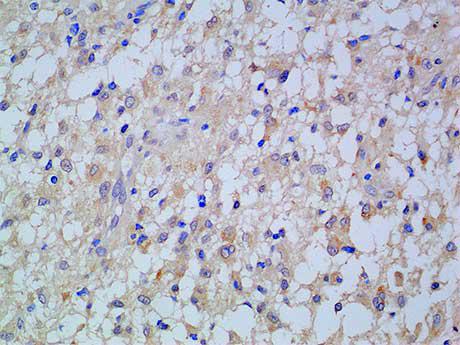

Autophagy is generally activated by conditions of nutrient deprivation but has also been associated with a number of physiological processes including development, differentiation, neurodegeneration, infection, and cancer. Atg13 (ATG13 autophagy related 13 homolog) is a 517 amino acid hosphoprotein

belonging to the ATG13 metazoan family.Atg13 functions as an autophagy factor required for autophagosome formation. Atg13 is a target of the TOR kinase signaling pathway, which mediates autophagy by controlling phosphorylation of Atg13 and ULK1, and by regulating the Atg13-ULK1-RB1CC1 complex.Atg13 also functions as a component of another complex, the ULK1-Atg13 complex, which regulates Atg9 and Atg23 retrieval transport from the pre-autophagosomal structure.